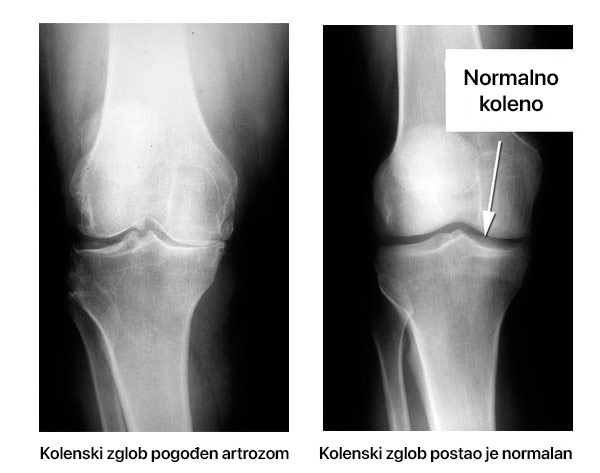

Obnova kolena pogođenog aterosklerozom. Pacijent je koristio i nakon jednog meseca, struktura i pokretljivost zgloba su potpuno obnovljeni. Bol je potpuno nestao.